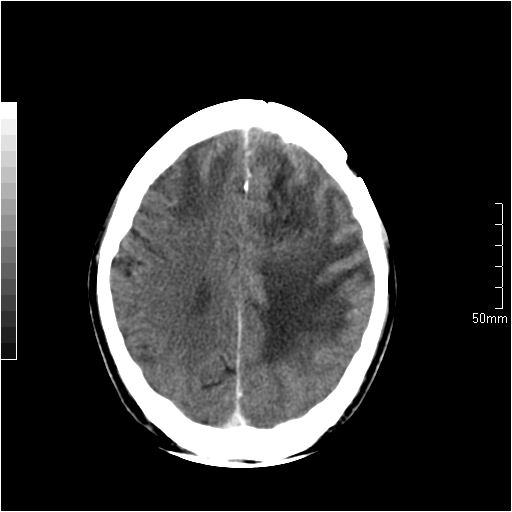

以下是引用天南地北在2007-6-25 12:39:00的发言:[br]有占位效应[br]支持术后复发

以下是引用zjzjr在2007-6-25 12:38:00的发言:[br]左侧复发,右侧转移。